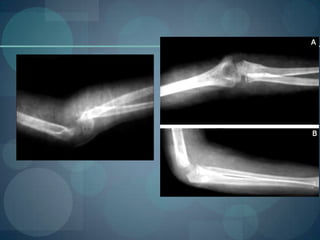

Caso clinico 5Paciente femenina, de 4 años de edad, con antecedentes de salud, que presentó caída desus pies, acude con dolor intenso en antebrazo, deformidad del codo y el antebrazoderecho con limitación de la flexión del codo, sin afectación de nervios periféricos. Sele realizó radiografía de antebrazo total que incluyó codo (Fig.1). Se diagnosticó unaluxo-fractura de Monteggiatipo I según Bado.

Cual es la fractura de monteggio  tipo 1Fractura del tercio proximal o medio del cúbito con angulación anteriorde los fragmentos fracturaros y luxación anterior de la cúpula radial

Caso clinico 5Pacientefemenina, de 4 años de edad, con antecedentes de salud, que presentó caída desus pies, acude con dolor intenso en antebrazo, deformidad del codo y el antebrazoderecho con limitación de la flexión del codo, sin afectación de nervios periféricos. Sele realizó radiografía de antebrazo total que incluyó codo (Fig.1). Se diagnosticó unaluxo-fractura de Monteggiatipo I según Bado.

Cual es lafractura de monteggio tipo 1Fractura del tercio proximal o medio del cúbito con angulación anteriorde los fragmentos fracturaros y luxación anterior de la cúpula radial